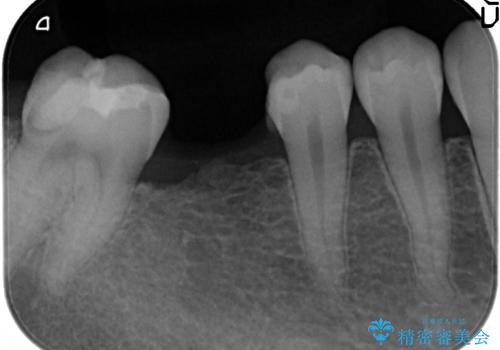

吸収した骨を造骨にて補い、インプラントによる機能回復を計画します。

歯を失ってからの時間が経過し骨が吸収してしまっていても、造骨を行うことで予知性の高いインプラント治療を行うことができます。